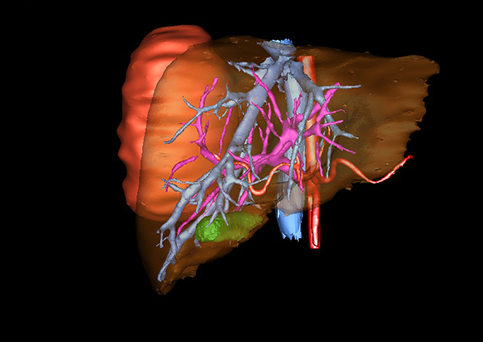

图1 位于肝右的叶肝母细胞瘤, 6个月,男婴

目前常用的检查方法有B超检查、CT、MRI、血管造影等。与其它的腹部肿块的诊断不同,对于小儿肝母细胞瘤血管造影具有重要的意义,可以作为手术前介入治疗的手段,也可为手术提供非常有效的影像学指导,但技术要求高,操作较复杂,且给患儿带来一定的痛苦。近年借助计算机辅助手术系统进行CT原始影像三维重建、手术规划和计算机虚拟手术技术,为精准肝脏手术提供了极为有效的技术支持。

近年来由于数字医学的发展,基于可视化三维重建技术的计算机辅助手术系统极大推进了小儿肝脏肿瘤的精准手术的进步。可以立体透视肝脏解剖、精确掌握肝段的边界、精确测算肝段乃至任意血管所支配的功能体积、准确定位病灶及其与邻近血管的解剖关系,最终对不同手术方案进行比较、筛选和优化。因此,计算机辅助手术规划系统是实现精准肝切除的有力辅助工具,是未来数字外科、精准外科等21世纪外科新理念的重要技术支撑。

计算机辅助手术规划系统具有良好的操作可行性、计算准确性和三维显示效果,可半透明、交互式显示真实的肝内立体解剖关系和空间管道变异,准确计算肝内管道的直径、走行角度,两点间的垂直距离,和任意血管的支配或引流范围等传统二维影像无法获取的信息,有助于实施个体化手术,提高了手术的确定性、预见性和可控性。计算机辅助手术规划系统可直观显示预留肝脏的结构和功能,并可通过虚拟切割功能辅助术者对手术方案进行蹄选和优化,系统评估手术风险和制定对策,改变了部分二维规划的术式和切除范围,使部分二维规划认为不能切除的患者成功手术,提高了手术的根治性、安全性和病变的可切除性,更加符合精准肝脏外科的术前规划要求。详见第11章。

随着计算机技术及影像检查技术的不断发展,以精确的术前影像学和功能评估、精细的手术操作为核心的精准肝切除技术日益受到重视。基于数字医学的计算机辅助手术技术(computer-assisted surgery,CAS)则是实现肝脏精准手术操作的基础。计算机辅助手术系统(CAS)可将术前二维(two dimensional,2D)的CT/MRI影像数据进行三维(three dimensional,3D)重建,建立个体化的肝脏三维解剖模型,清晰显示肝脏内脉管系统的走行及解剖关系,还原病灶与其周围脉管结构的立体解剖构象,准确地对病变进行定位、定性和评估,制定合理、定量的手术方案,实施个体化的肝脏血管取舍分配方案及实施精准肝脏手术。一般认为CAS包括:创建虚拟的患者的图像;患者图像的分析与深度处理;诊断、手术前规划、手术步骤的模拟;术中实时导航。应用本技术后,由于可以更清晰地看出肿瘤的界限,特别是根据肝血管的显影,判断出肿瘤与门静脉及肝静脉的关系以在手术前较准确地估计出手术成功切除的可行性。以往部分根据普通强化CT判断无法手术的病例而被评估为可以成功切除并手术成功。